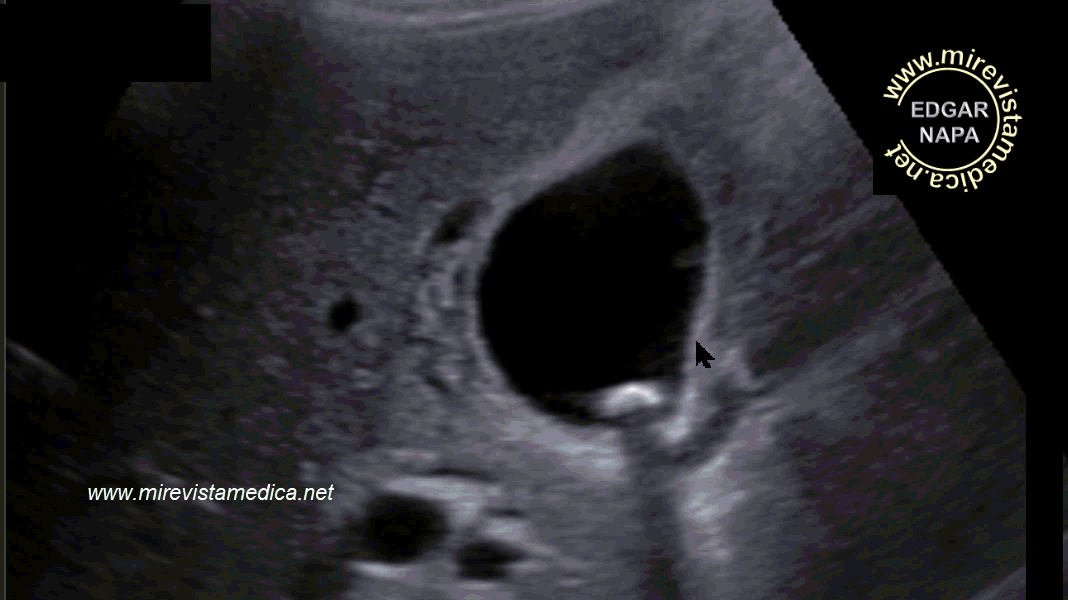

Hallazgos por ultrasonido (US_) :

- imagen hiperecogénica, movil, de márgenes circunscritos que deja sombra acústica posterior (litiasis).

- Signo de Murphy ecográfico. Pain and tenderness with transducer pressure directly over gallbladder.

- Engrosamiento de pared vesicular (se le denomina así cuando es > 3 mm). Hazy delineation of GB wall with echogenic pericholecystic fat.